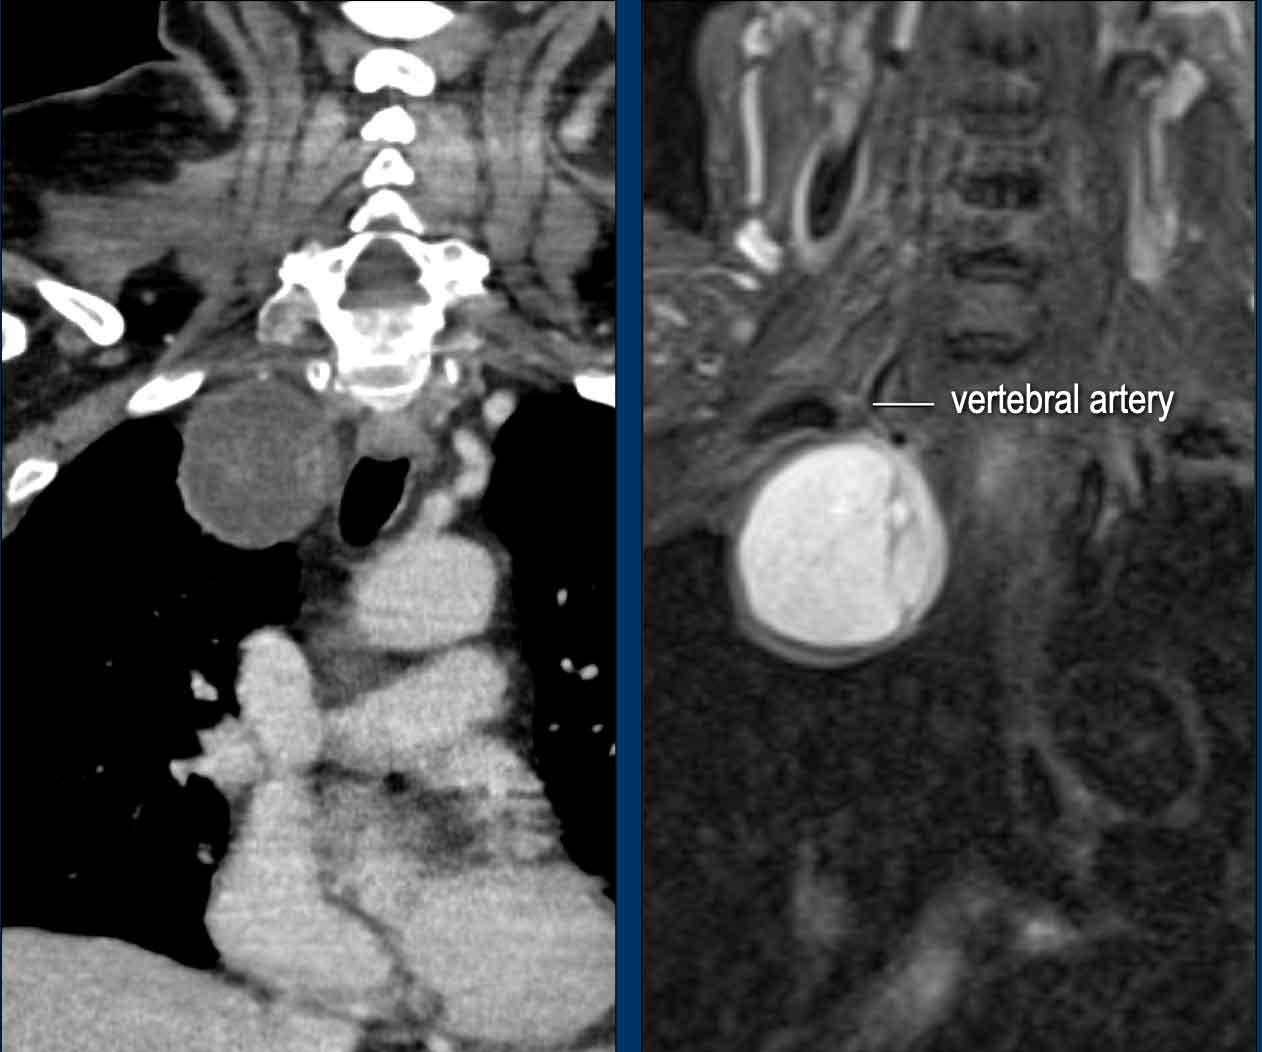

Hình ảnh của một phụ nữ 55 tuổi với triệu chứng đau vai và cổ.

Hình ảnh

X-quang cột sống cổ

và cột sống ngực cho thấy một khối u chiếu lên vùng đỉnh

phổi phải.

Dựa vào dấu hiệu cổ-ngực, khối u nhiều khả năng xuất phát

từ trung thất sau.

Tiếp tục với các hình ảnh tiếp theo…

Tại khám thần kinh, hội chứng Horner bên phải được phát hiện.

Đầu tiên, chụp CT được thực hiện vì nghi ngờ có thể có ác tính.

CT cho thấy một tổn thương có vỏ bao ở trung thất sau.

Không có hạch bạch huyết to.

MRI cho thấy tổn thương giới hạn rõ với tín hiệu tăng trên T2 gợi ý nang hoặc hoại tử.

Continue…

Images

The sagittal T1W image shows rim enhancement.

Kết luận

Tổn thương có hiệu ứng khối lên hạch cổ dưới bên phải và đây là nguyên nhân gây ra hội chứng Horner.

Chẩn đoán có khả năng nhất là u bao thần kinh (schwannoma) cũ.